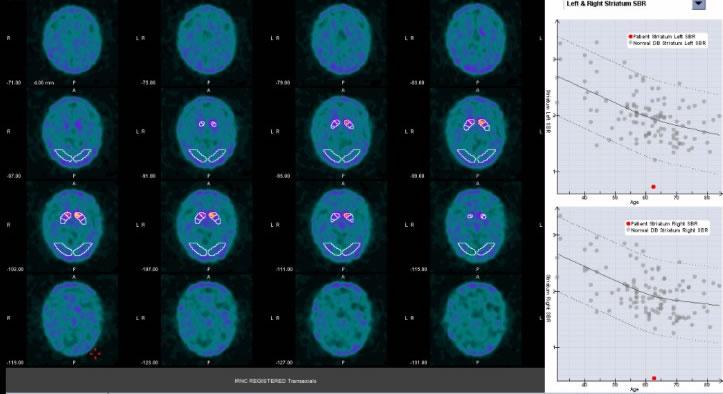

NEW!健常者データを用いた診断補助アプリケーション(Dat QUANT)

健常者の頭部(線条体集積)データを用いた診断補助アプリケーションにより、レビー認知症、パーキンソン病等の診断が容易となります。